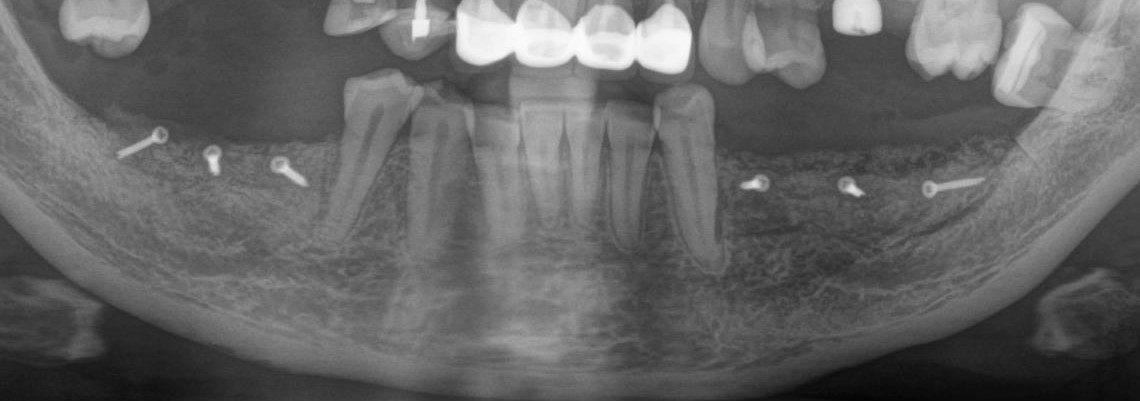

Рентгеновский снимок после операции (расщепление было проведено с двух сторон):

Снимок, сделанный через 5 месяцев после операции:

Обратите внимание, как изменился цвет кости. Она полностью восстановилась. На снимке этот участок стал белее.